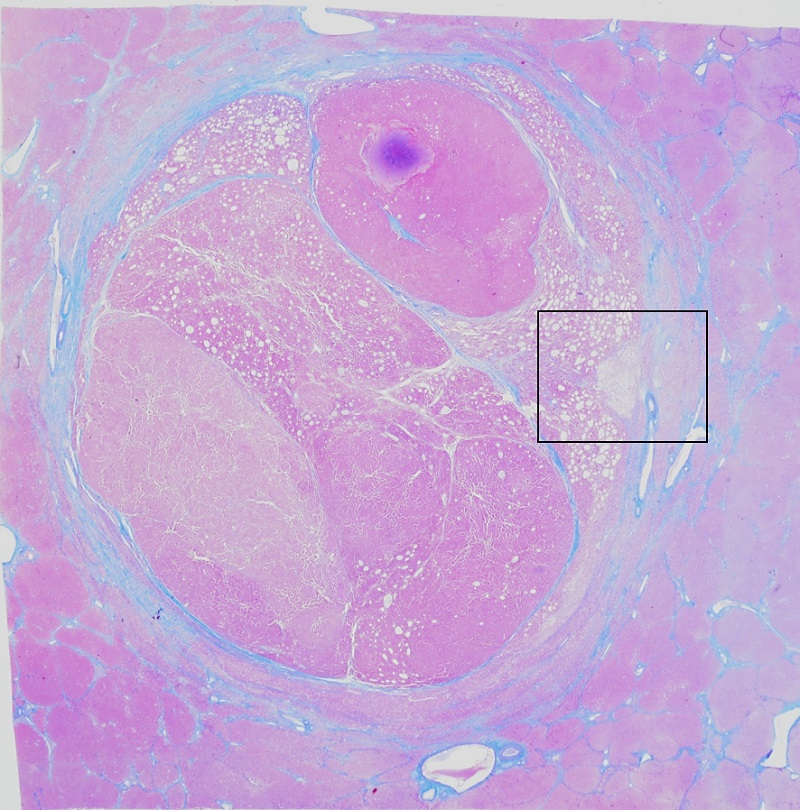

市 原:ありがとうございます.今回の病変は,比較的高エコー領域が目立つHCCです.ルーペ像も見てみましょう(図2).膠原線維の被膜に全周を覆われたHCCで,内部にはキラキラと白い部分があちこちに見られます.

図2 Azan染色のルーペ像

青く染まる膠原線維によって全周を覆われた腫瘍.白くキラキラした成分が3時方向や11時方向などに認められる.